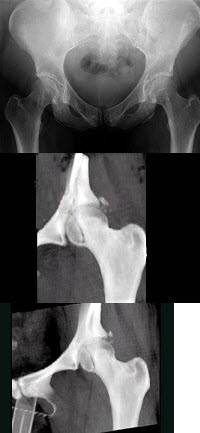

121、单项选择题

女,17岁,有支气管炎,蛋白尿(++++),结合图片,最可能的诊断()

A.特发性含铁血黄素沉着

B.韦格肉芽肿

C.肺梗死

D.特发性肺间质纤维化

E.肺-肾综合征

146、单项选择题

男,5岁。发热、胸痛、胸闷、气促。X线检查如图,最可能的诊断为()

A.右侧胸膜间皮瘤

B.右侧肺脓肿

C.右侧包裹性积液

D.右侧肺不张

E.右侧气胸